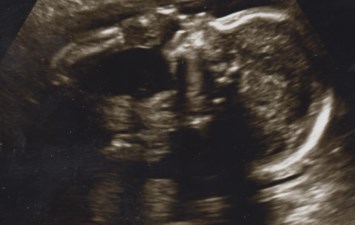

Braelyn Arthur Gene Ford

2 December, 2014 – 2 December, 2014